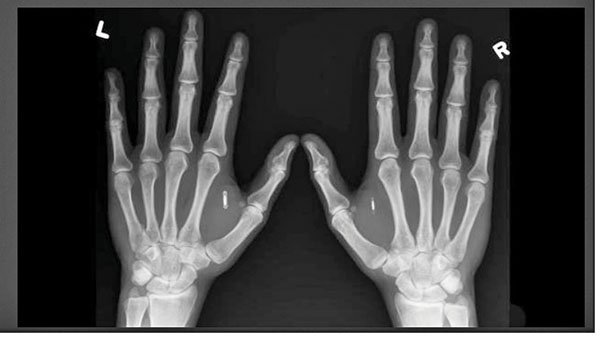

فرانک اسوین، روزنامهنگار انگلیسی در مقاله «چرا من به یک ریزتراشه کاشتنی نیاز دارم؟» به بیان دیدگاههای خود در این زمینه پرداخته است. اسوین توضیح میدهد: «زمانی که تراشه RFID از کارتهای هوشمندی که میلیونها نفر در انگلستان برای پرداخت هزینه حمل و نقل و مترو از آن استفاده میکنند، بر روی دست مردم قرار گیرد، آنگاه مردم میتوانند با حرکت موجدار دست خود قفل جایگاه ورود به مترو را باز کنند. فرآیندی که شبیه به حرکات جادویی است.» جالب آنکه فرانک خود به شخصه سعی کرده است این تراشه را در زیر پوست خود جایگذاری کند، اما در این راه با شکست روبهرو شده است. اما در نمونه دیگری آمال گرافسترا بنیانگذار شرکت Dangerous Things که در زمینه کاشتنیهای RFID تخصص دارد، در این زمینه موفقیتهایی را بهدست آورده است. وی موفق به کاشت تراشههایی در بخش گوشتی دستان خود شد. (بین انگشت شست و انگشت اشاره) جالب آنکه آمال برای اینکه همیشه به کیف پول خود دسترسی داشته باشد، تصمیم گرفت از دو تراشه RFID در دستان خود استفاده کند. (شکل 1)

شکل 1: تراشههای قرارگرفته در دو دست آمال گرافسترا

تراشهای با قابلیت بازنویسی در دست راست قرار دارد که برای ذخیرهسازی مقدار مختصری از دادهها استفاده میشود، در حالی که تراشه دوم در دست چپ قرار دارد و شماره شناسایی آمال را در خود جای داده است. آمال از کاشتنیهای خود برای باز کردن درها، تلفنها، ثبت اطلاعات کامپیوترها و روشن کردن وسایل نقلیه، تنها از یک حرکت موجدار دست خود استفاده میکند. او همچنین، توانایی بهاشتراکگذاری جزییات مخاطبان و صفحات شبکههای اجتماعی خودش با دوستانش را دارد. وی به آنها اجازه میدهد کاشتنی او را با استفاده از یک اسمارتفون یا تبلت اندرویدی یا ویندوزی که مجهز به NFC است، اسکن کنند.